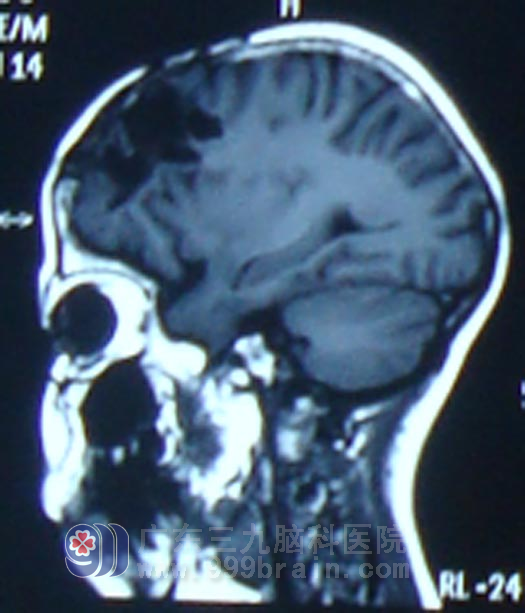

术后